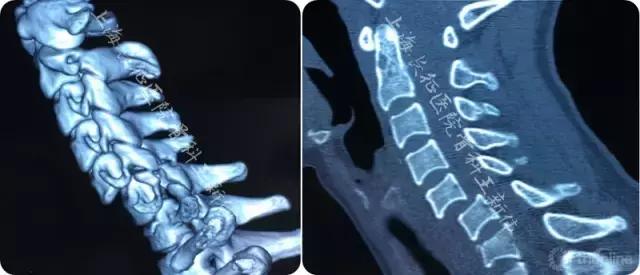

第一次术前影像学检查 :

第一次术前颈椎X线正侧位片

第一次术前颈椎CT三维重建

第一次术后颈椎CT三维重建,可见C6/7双侧仍存在关节绞锁